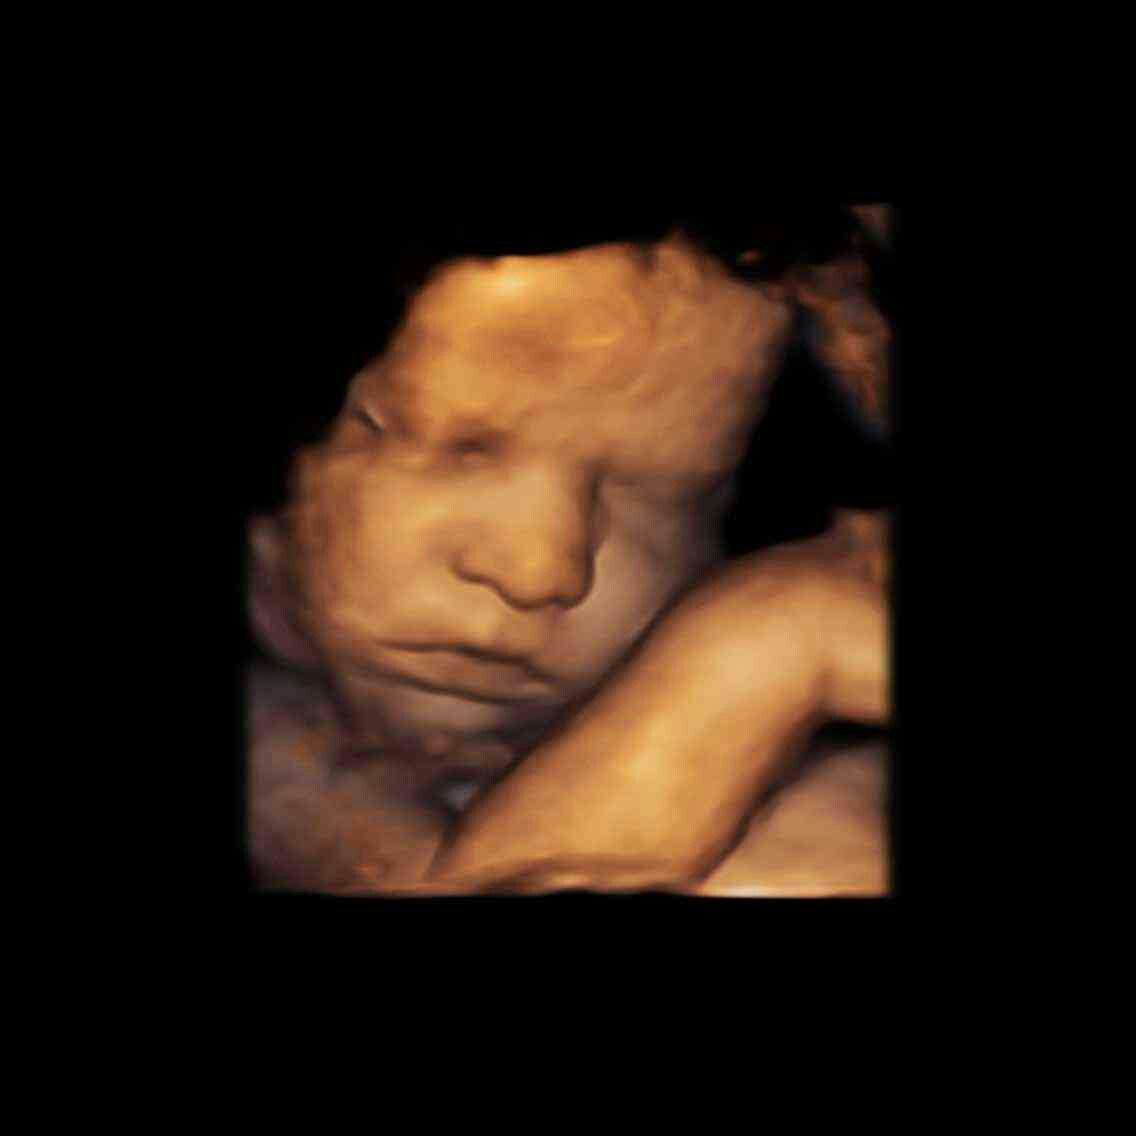

明天就是35周,还有36天就宝宝出生啦!好开心啊!现在的宝宝在肚子里面就这么大了!有没有宝妈跟我一 明天就是35周,还有36天就宝宝出生啦!好开心啊!现在的宝宝在肚子里面就这么大了!有没有宝妈跟我一样的。预产期9月18号。 点击展开 137*****903_3r1O 2016-08-11 16:15 为您推荐: 其他回答 哦。。。。 宋宋妈妈 2016-08-11 17:45 恭喜恭喜啊 杨夫人 、 2016-08-11 17:26 一祝福你 呦,呵呵 183*****531_ahkm 2016-08-11 17:24 恭喜恭喜!祝健康好孕! 攖霏宝贝 2016-08-11 17:12 鼻子嘴巴好大 小臭女 2016-08-11 17:00 加载更多 相关问题 明天是宝宝29周,宝宝在肚子里经常动,请问宝妈们有没有和我一样的? 宝宝今天吃的拉肚子要影响明天打乙肝吗 宝宝五个月了明天打预防针,有点闹肚子给她喝了点冲剂,请问明天可以去打吗?